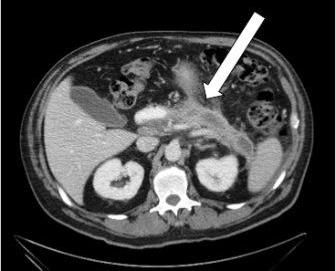

The patient was aggressively managed with IV fluids and IV imipenem and was monitored in the ICU. He remained clinically stable and after 2 days was downgraded to a regular ward, taken off antibiotic therapy, and clinically monitored. A subsequent esophagogastroduodenoscopy (EGD) revealed a posterior wall penetrating duodenal ulcer >2 cm in diameter (Figure 3). The patient remained asymptomatic throughout his hospital course, without evidence of clinical or hemodynamic compromise. He was able to tolerate oral intake within 2 days of admission. He was discharged in stable condition with plans to complete high-dose PPI therapy. He has remained stable and emphysematous pancreatitis has resolved (Figure 4).

Figure 3

In the case presented here, the finding of a penetrating duodenal ulcer provided a possible cause for the presence of air in the pancreas. This finding is similar to that seen in approximately half of patients in a small case series reported in 2009.3 We believe that in clinically stable patients with emphysematous pancreatitis, an EGD should be performed for further evaluation. In those without clinical or laboratory evidence of infection, we recommend limiting the use of broad-spectrum antibiotics and instead propose conservative supportive care.